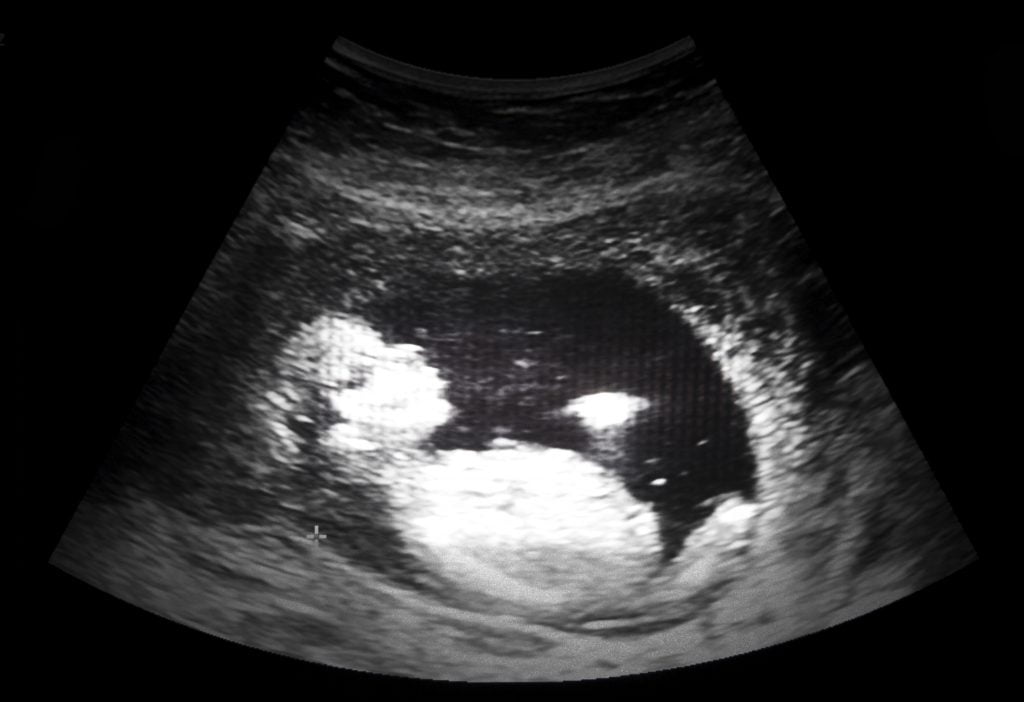

The 20-week ultrasound appointment lasts between an hour and an hour and a half. The technician measures every inch of the baby’s developing body, which is roughly the length of a banana. All of their measurements and photos are then retrospectively reviewed by a radiologist for “concerning images.”

“First of all, there is a focus in the heart,” the doctor explained to Samantha. “You may have noticed the technician taking extra pictures. Second, his fingertips seem to be curved. It is not fully clear, but it does look like a few of the tips are rounded. And third, he is measuring one week behind in his arm and legs.”

These are all “soft markers” for Down syndrome. Samantha was sent to a high-risk clinic for another ultrasound and to meet with a genetic counselor. “We fully support you in whatever decision you would like to make,” the doctor said.